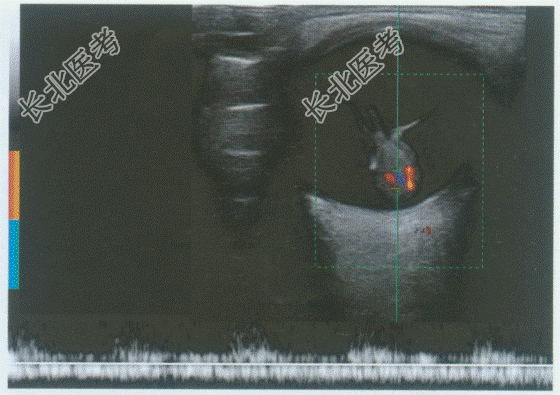

- 单项选择题男性,38岁, 自述右眼视力下降来诊。临床物理检查:发现患者颜面部血管瘤, 余全身检查未见异常。超声综合描述:右眼后极部可见0.6cm×0.8cm孤立型椭圆形中强回声, 边界清晰,内部回声均匀。与周围组织之间界限清晰, 后方无明显声衰减,中强回声旁可见带状强回声与视盘回声相连, CDFI:中强回声内可见丰富的血流信号, 以基底部分布最为明显,PW: 为动脉血流频谱。见下彩图。超声提示:

A、葡萄膜恶性黑色素瘤合并视网膜脱离

B、葡萄膜色素痣合并视网膜脱离

C、视网膜静脉周围炎

D、脉络膜血管瘤合并视网膜脱离

E、眼脉络膜脱离